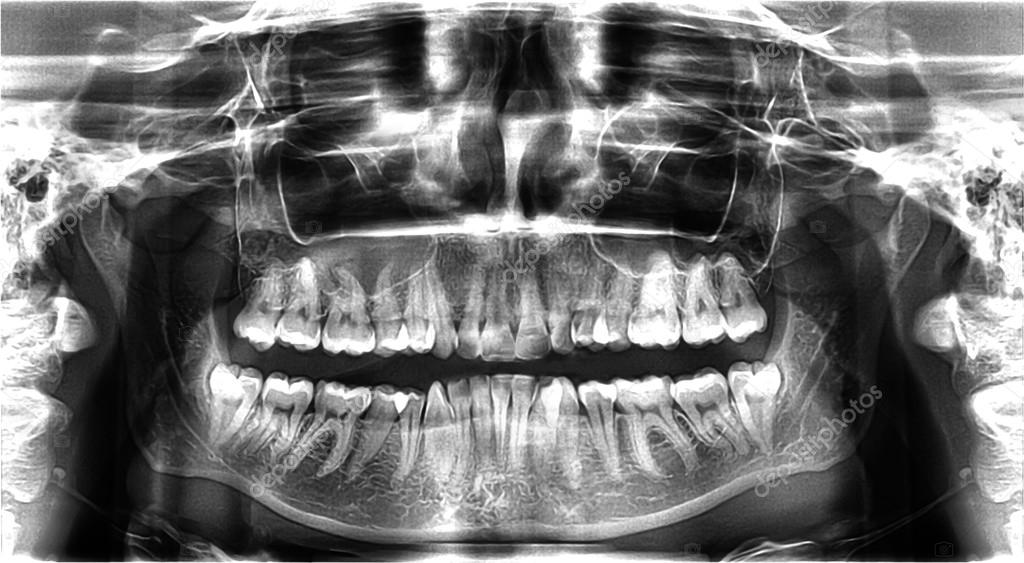

Панорамный снимок (или ортопантомограмма) – это плоское двухмерное изображение челюстей, зубов, гайморовых пазух и даже височно-нижнечелюстного сустава. Поскольку поверхность челюстей изогнутая, на плоской рентгеновской плёнке снимок отображается неравномерно увеличенным в боковых и передних отделах челюстей – то есть слегка деформированым.

- Двухмерный вид не даёт информацию во всех плоскостях — для этого нужен 3D КТ снимок.

- Недостаточно чёткое отображение мелких деталей.

- Искажения, наслоение теней от других костей и позвоночника, смещения и затемнения неизбежны.

- Лишь ориентировочное представление о размерах корней зубов и расстоянии до важнейших анатомических образований (канал нижнечелюстного нерва и гайморова пазуха), из-за того, что изображение растянуто неравномерно в боковых и передних отделах.